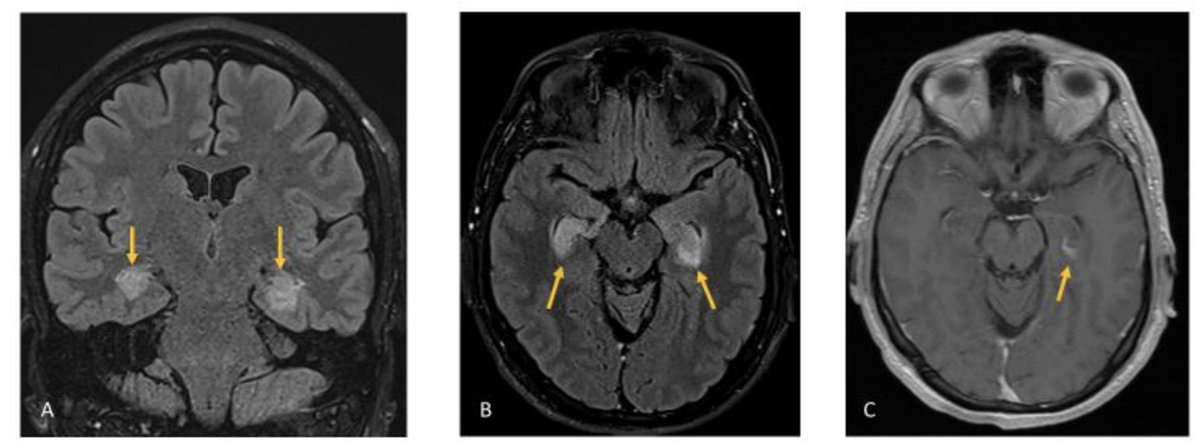

🧠 New in Practical Neurology: Paraneoplastic KLHL11 antibody encephalitis presenting with progressive tinnitus, hearing loss, and cerebellar ataxia. KLHL11-IgG - strongly linked to testicular germ cell tumours - shows a distinctive “sparkles” pattern on immunofluorescence 🔬